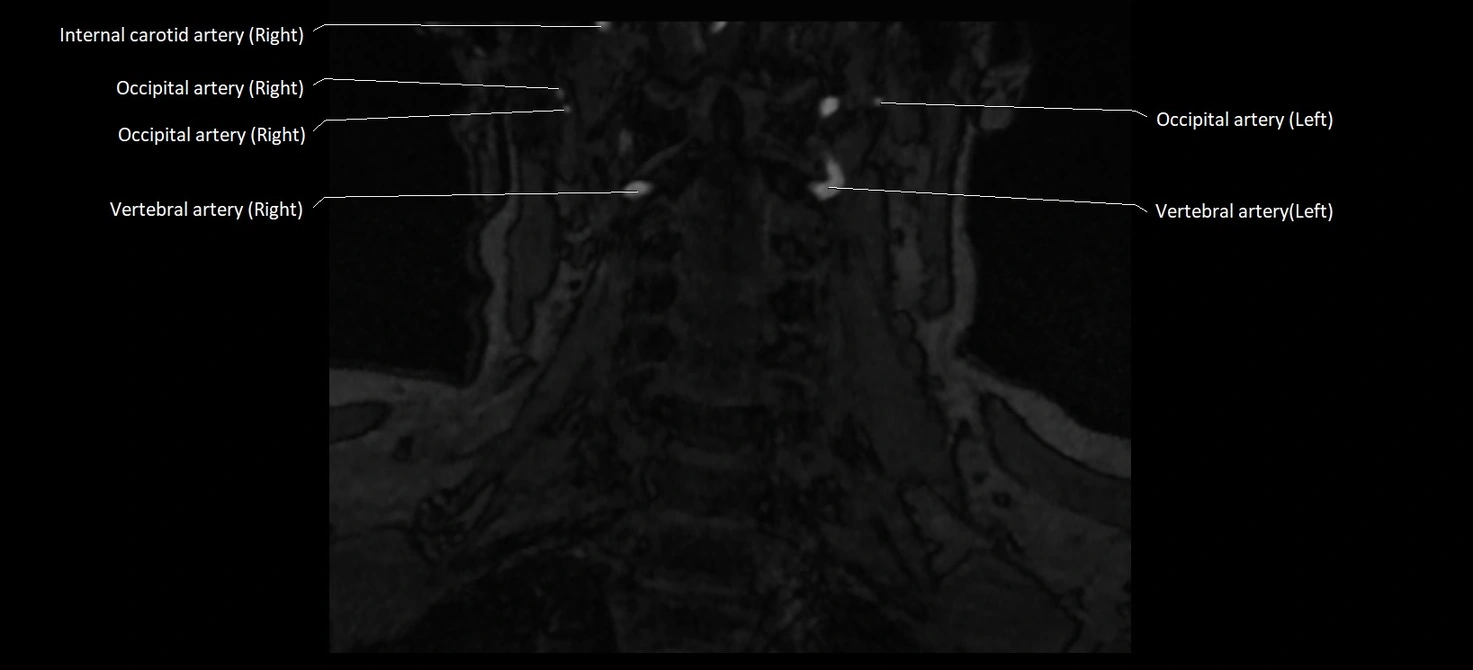

MRI images

image